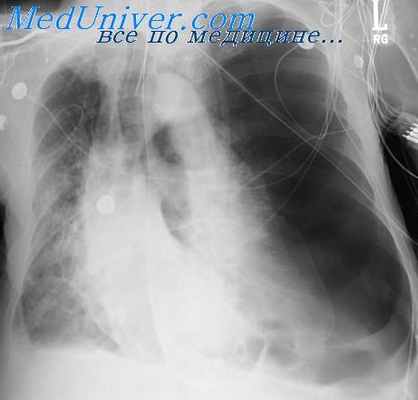

Диагноз устанавливают на основании анамнеза, характерных жалоб и клинических симптомов. Учитывается соответствие использованного режима декомпрессии условиям пребывания под водой или перед подъемом на высоту, а также индивидуальная устойчивость больного к декомпрессионным воздействиям. Д. б. следует дифференцировать с баротравмой (Баротравма) легких (характерны потеря сознания, пенистая кровавая мокрота и резкие боли при дыхании), наркотическим действием индифферентных газов (отсутствие болевых симптомов) и отравлением кислородом, при котором наблюдаются судороги и потеря сознания (см. Гипероксия). У больных со средней и тяжелой формой Д. б. часто отмечается повышение гематокритного числа. Рентгенодиагностика Д. б. имеет относительное значение. Лишь в отдельных случаях обнаруживают газовые пузырьки в полостях суставов, сухожильных влагалищах, фасциях и околососудистых образованиях. Иногда выявляют характерные асептические некрозы трубчатых костей и деформирующий остеоартроз — последствия перенесенной Д. б. С диагностической целью успешно используют ультразвуковой метод обнаружения в крови газовых пузырьков.

Техника и последовательность судебно-медицинского исследования трупа при подозрении на Д. б. имеют свои особенности. Перед вскрытием рекомендуется провести рентгенографию грудной клетки трупа, при которой могут быть обнаружены явления газовой эмболии сердца. Само вскрытие необходимо осуществлять как можно раньше, т.е. до появления гнилостных изменений, существенно меняющих картину. Обязательным является проведение пробы на газовую эмболию, для чего в полость перикарда наливают воду, а затем прокалывают под водой последовательно правые предсердие и желудочек, затем левые. Положительный результат, т. е. появление газовых пузырьков при проколе правых отделов сердца, указывает на быструю декомпрессию. При отрицательном результате рекомендуется провести пробу на газовую эмболию нижней полой вены. Для этого петли тонкой кишки оттесняют влево, в правую половину полости брюшины наливают воду и под водой разрезают париетальную брюшину над нижней полой веной и прокалывают ее стенки. Исследование трупа целесообразно дополнить проведением гистологического и судебно-химического (для обнаружения или исключения наличия этанола и окиси углерода) исследований.